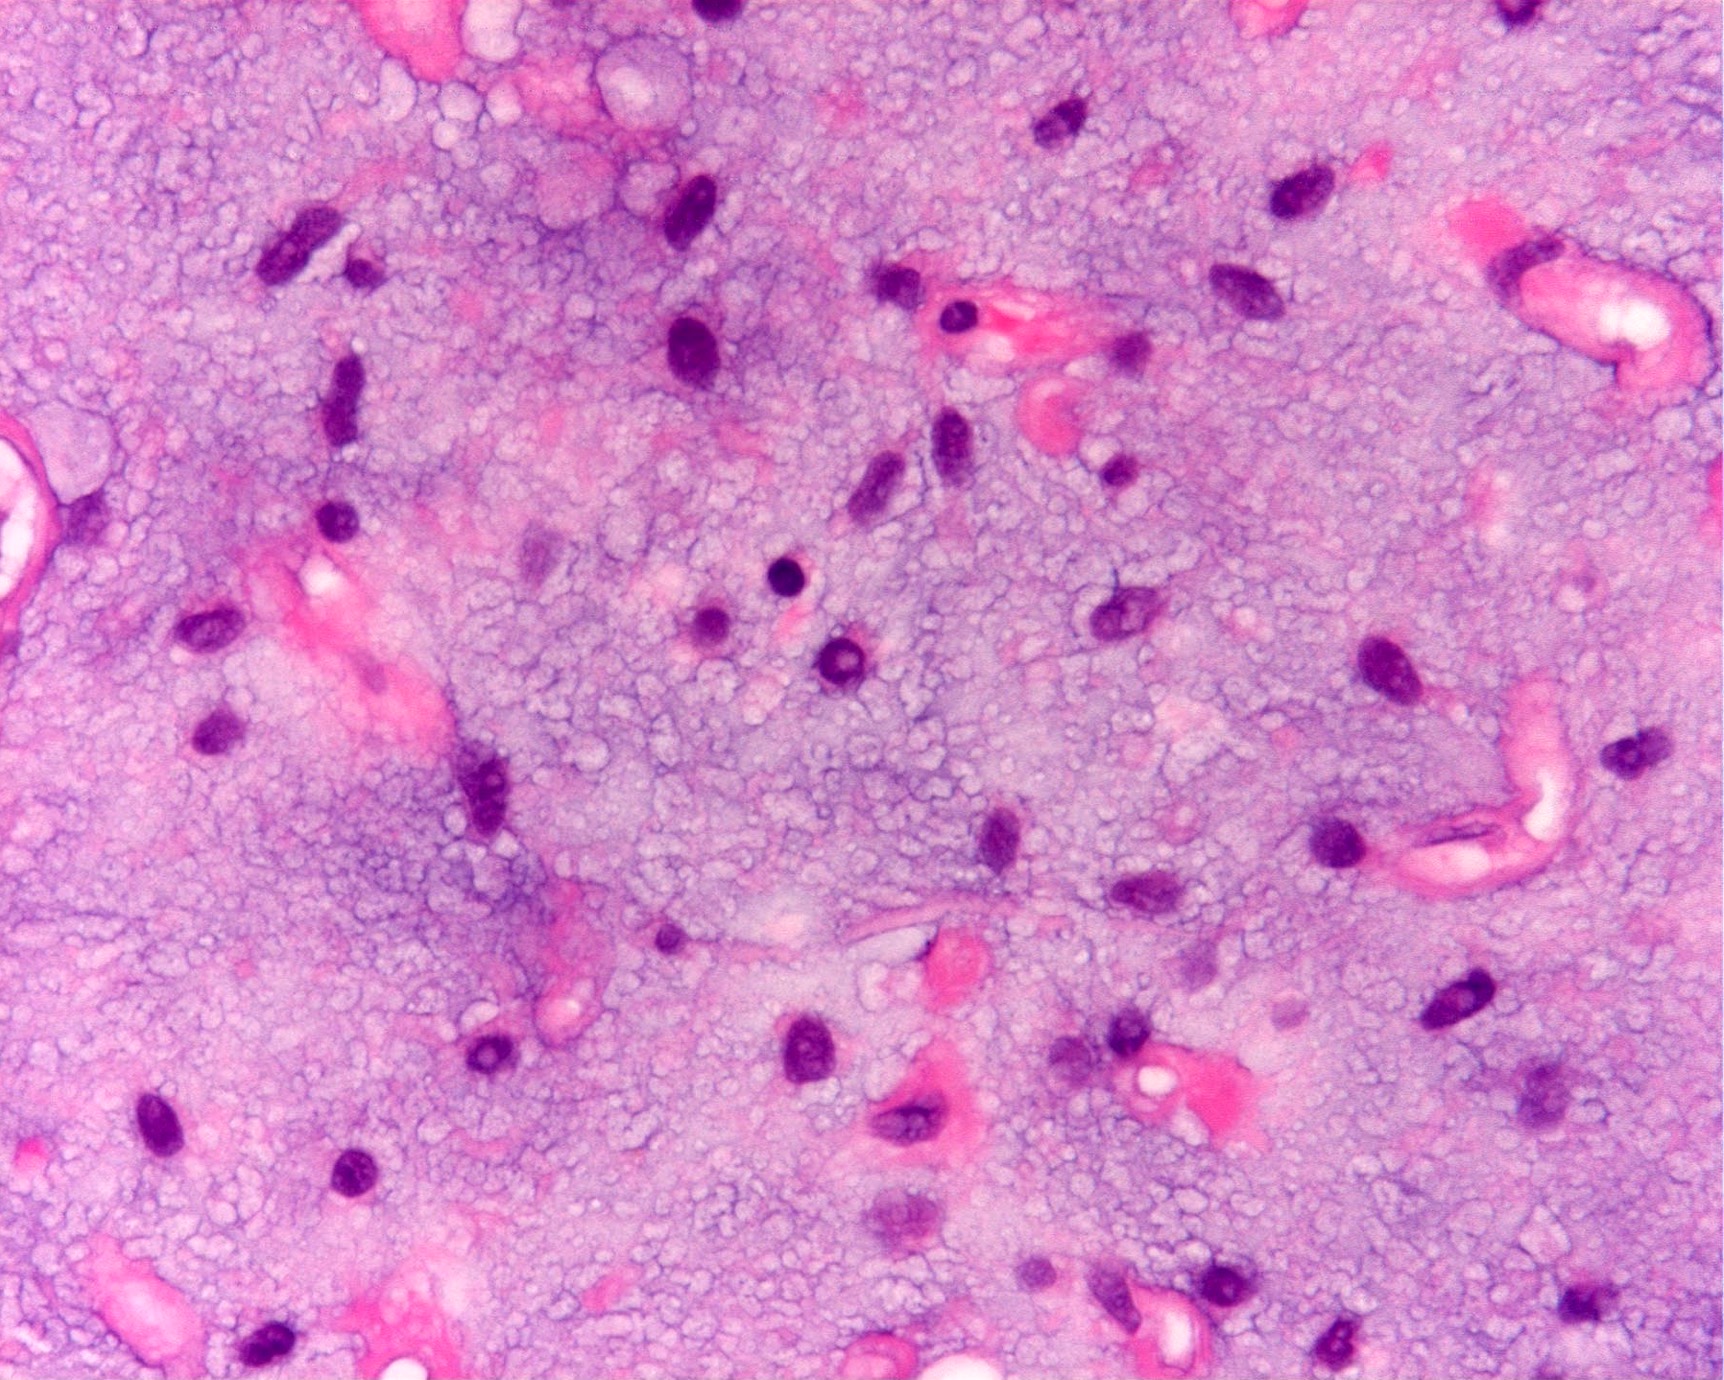

Microscopic (histologic) description

- Numerous signet ring lipoblasts, particularly at periphery of lobules

- This imparts a lipoblastoma-like appearance (see Differential diagnosis)

- Mucoid matrix is rich in hyaluronic acid that may form large mucoid pools (so called pulmonary edema pattern)

- Paucicellular with monomorphic, stellate or fusiform shaped cells without atypia; striking in their blandness, so much so that any significant pleomorphism should cause one to pause

- Prominent plexiform vasculature (delicate thin walled arborizing and curving capillaries that form a network reminiscent of chicken wire fencing)

D. Majority of cases harbor t(12;16) FUS::DDIT3 gene fusion. The microscopic image depicts a low grade myxoid liposarcoma characterized by a proliferation of bland stellate tumor cells embedded in a myxoid matrix with a prominent plexiform capillary network and scattered signet ring lipoblasts. There is no mitotic activity or pleomorphism. The majority of cases of myxoid liposarcoma harbor a t(12;16) FUS::DDIT3 gene fusion. Answers B and C are incorrect because the t(9;22) EWSR1::NR4A3 gene fusion is characteristic of extraskeletal myxoid chondrosarcoma and the t(7;16) FUS::CREB3L2 gene fusion is characteristic of low grade fibromyxoid sarcoma. Answer E is incorrect because classification of myxoid liposarcoma as high grade requires > 5% of the sampled lesion to consist of a hypercellular round cell component according to the WHO. Cases with borderline round cell component (< 5%) are regarded as having areas of transition, a designation of unclear diagnostic significance. Answer A is incorrect because immunohistochemistry for MDM2 is negative in myxoid liposarcomas.